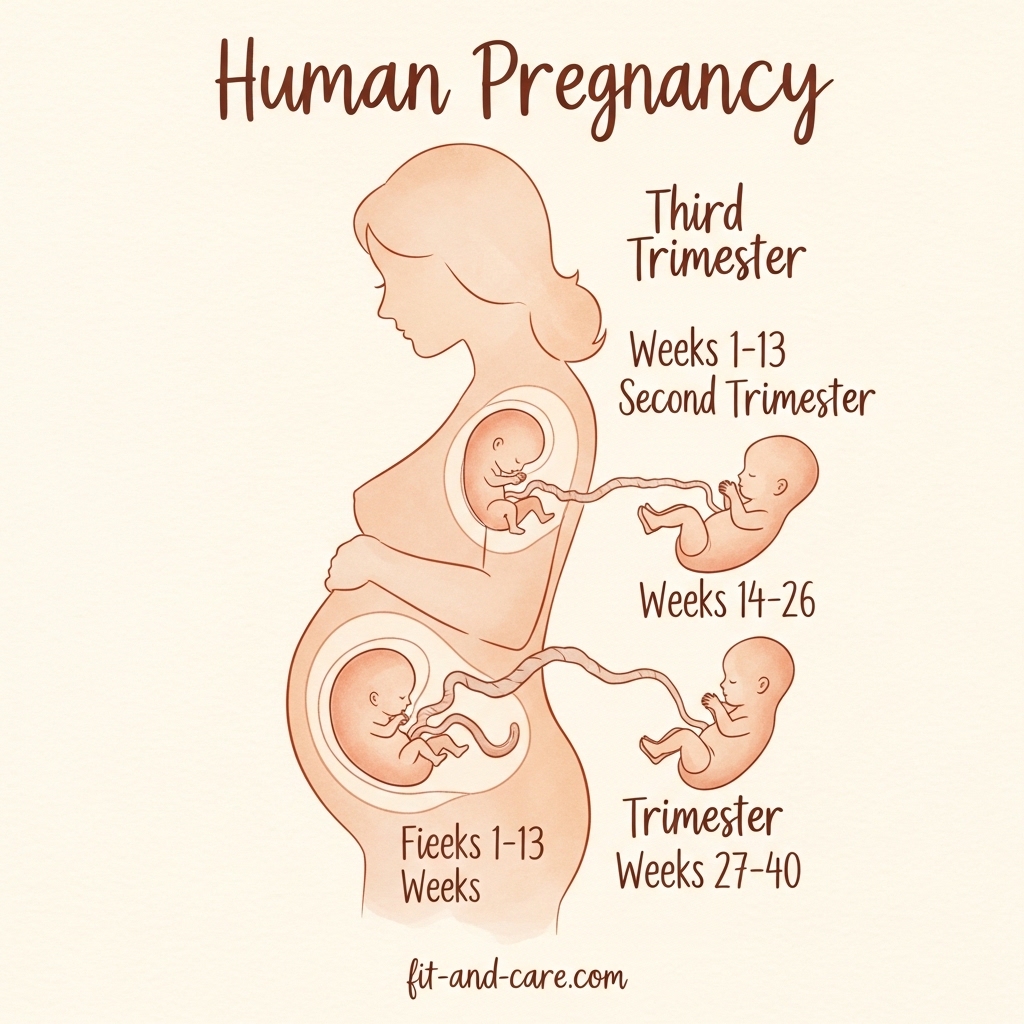

The Three Trimesters of Pregnancy: What to Expect

First Trimester (Weeks 1–13): The Foundation

There’s a lot of cellular activity in the first trimester. Within 13 weeks, your baby grows from a small cluster of cells to a fully grown fetus with developed limbs, a beating heart, and functioning organs.

Second Trimester (Weeks 14–26): The Golden Period

The second trimester is when most women feel better. The baby bump seems to grow, energy returns, and morning sickness fades. This trimester also signals the first stage of your baby’s motion, a stage called quickening that usually occurs between weeks 18 and 22.

Third Trimester (Weeks 27–40): The Home Stretch

Your baby gains much of its body weight and finishes the last phases of development in the third trimester. As the baby grows swiftly, the mother’s physical needs rise during this trimester.